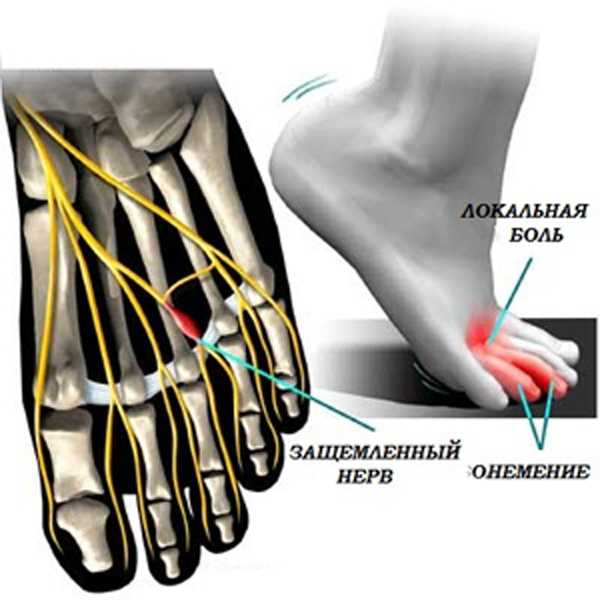

Эти заболевания ведут к ущемлению нервных окончаний, из-за чего образуются отеки, происходит патологический рост оболочки нервных волокон. Им становится сложно умещаться между связками ступни.

- боли, жжение, потеря чувствительности в области 3-го и 4-го пальцев;

- онемение ног;

- трудно ходить на высоких каблуках, при смене обуви дискомфорт проходит.

Запущенное заболевание характеризуется болями даже в покое. По отзывам пациентов, они сравнивают ходьбу в неудобной обуви, будто идешь по остриям камней.